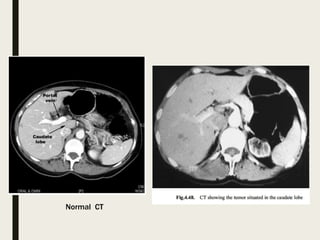

Normal CT

Hemangioma